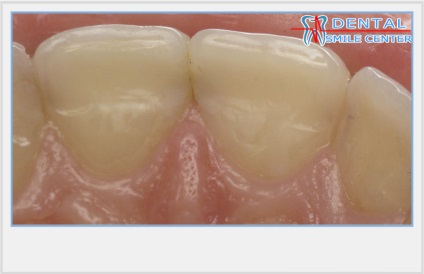

Klinikailag jelentős átmenetek vannak érintkezési felületek a vestibularis és száj felületén.

Az átmenet az érintkező felületek a vesztibuláris a henger felületét képez kellően hangsúlyos korlátozó reflexió zónában. Ez a zóna korlátozott, kivéve a marginális gerincek, és az egyenlítő a korona és a vágás.

Az átmenet az érintkező felületek az orális marginális gerincek képező felülete, alsó élei mentén a palatinális / lingvális fossa. Behajtott marginális gerincek megvédi fogköztisztító papillákban sérülésmentesen funkció még ha nem is nagyon szoros kapcsolati pontokat.

Az elülső fogak érintkeznek egymással az orális felületek, mivel vannak elrendezve egy ív. Következésképpen a kapcsolattartó pontok az elülső fogak mindig nyitott a vesztibuláris oldalon. Ez segít a helyreállítása elülső fogak, hogy újra a hatása családi fogak korona, képeznek egységes fogazat. Ezzel szemben, ennek elmulasztása azt eredményezi, a helyreállítás egy mesterséges növelése keresztirányú mérete koronák és létrehozza a vizuális hatás a „szilárd fehér fal” figyelhető meg a helyreállítás konstrukciók, ahol a koronák összekapcsolt (híd, amely a rúd szerkezet, fém ív).